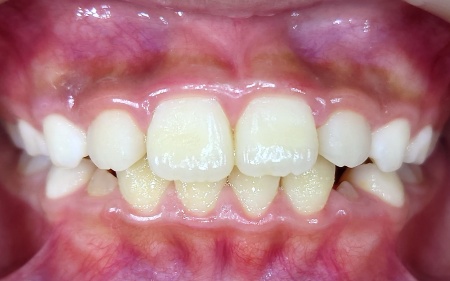

4歳女の子 歯並びを広げる装置とマウスピース型矯正装置を併用して左前歯のクロスバイトを改善した症例

拝見したところ、左前歯に上下の噛み合わせが逆になっているクロスバイトが見られました。

本来、正常な噛み合わせでは上の歯が下の歯に覆いかぶさる形になりますが、今回のケースでは左前歯の下の歯が上の歯よりも外側に出ていました。